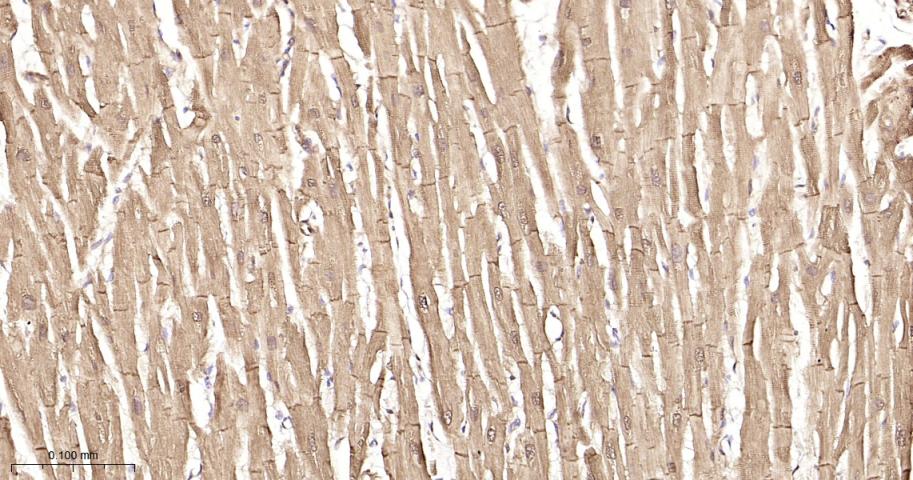

Paraformaldehyde-fixed, paraffin embedded Mouse Heart; Antigen retrieval by boiling in sodium citrate buffer (pH6.0) for 15 min; Antibody incubation with Hsp27 Monoclonal Antibody, Unconjugated(bsm-52757R) at 1:200 overnight at 4°C, followed by conjugation to the bs-0295G-HRP and DAB (C-0010) staining.

Paraformaldehyde-fixed, paraffin embedded Rat Heart; Antigen retrieval by boiling in sodium citrate buffer (pH6.0) for 15 min; Antibody incubation with Hsp27 Monoclonal Antibody, Unconjugated(bsm-52757R) at 1:200 overnight at 4°C, followed by conjugation to the bs-0295G-HRP and DAB (C-0010) staining.

Paraformaldehyde-fixed, paraffin embedded Human Heart; Antigen retrieval by boiling in sodium citrate buffer (pH6.0) for 15 min; Antibody incubation with Hsp27 Monoclonal Antibody, Unconjugated(bsm-52757R) at 1:200 overnight at 4°C, followed by conjugation to the bs-0295G-HRP and DAB (C-0010) staining.